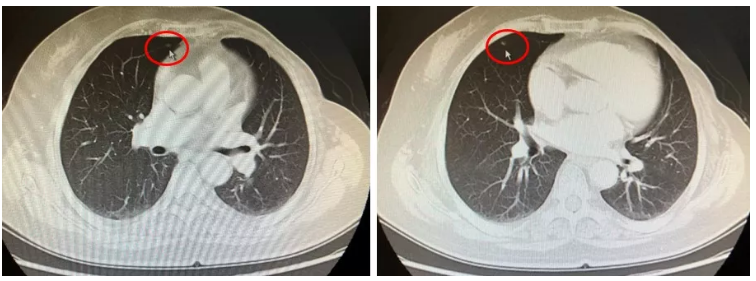

2017年12月患者常规复查,胸腹部增强CT示(图1):右肺中叶散在类结节影,大者约0.5cm;肝脏多发转移瘤,形态不规则,较前增多、增大,大者约2.7cm×2.4cm;左肾类圆形低密度影,约1.2cm,腹腔、腹膜后散在小淋巴结,大者短径约0.8cm;胸骨柄及胸骨体上段密度增高,结合病史考虑转移。2018年1月头颅MRI增强示:左侧小脑中脚强化类结节,警惕转移。骨扫描(ECT)示:胸骨柄及胸骨体上段转移灶,较前略缩小。结合病史综合疗效评价为病情进展(progressive disease,PD),PFS 1 为13.4个月。

图1 患者肺部转移灶影像学表现